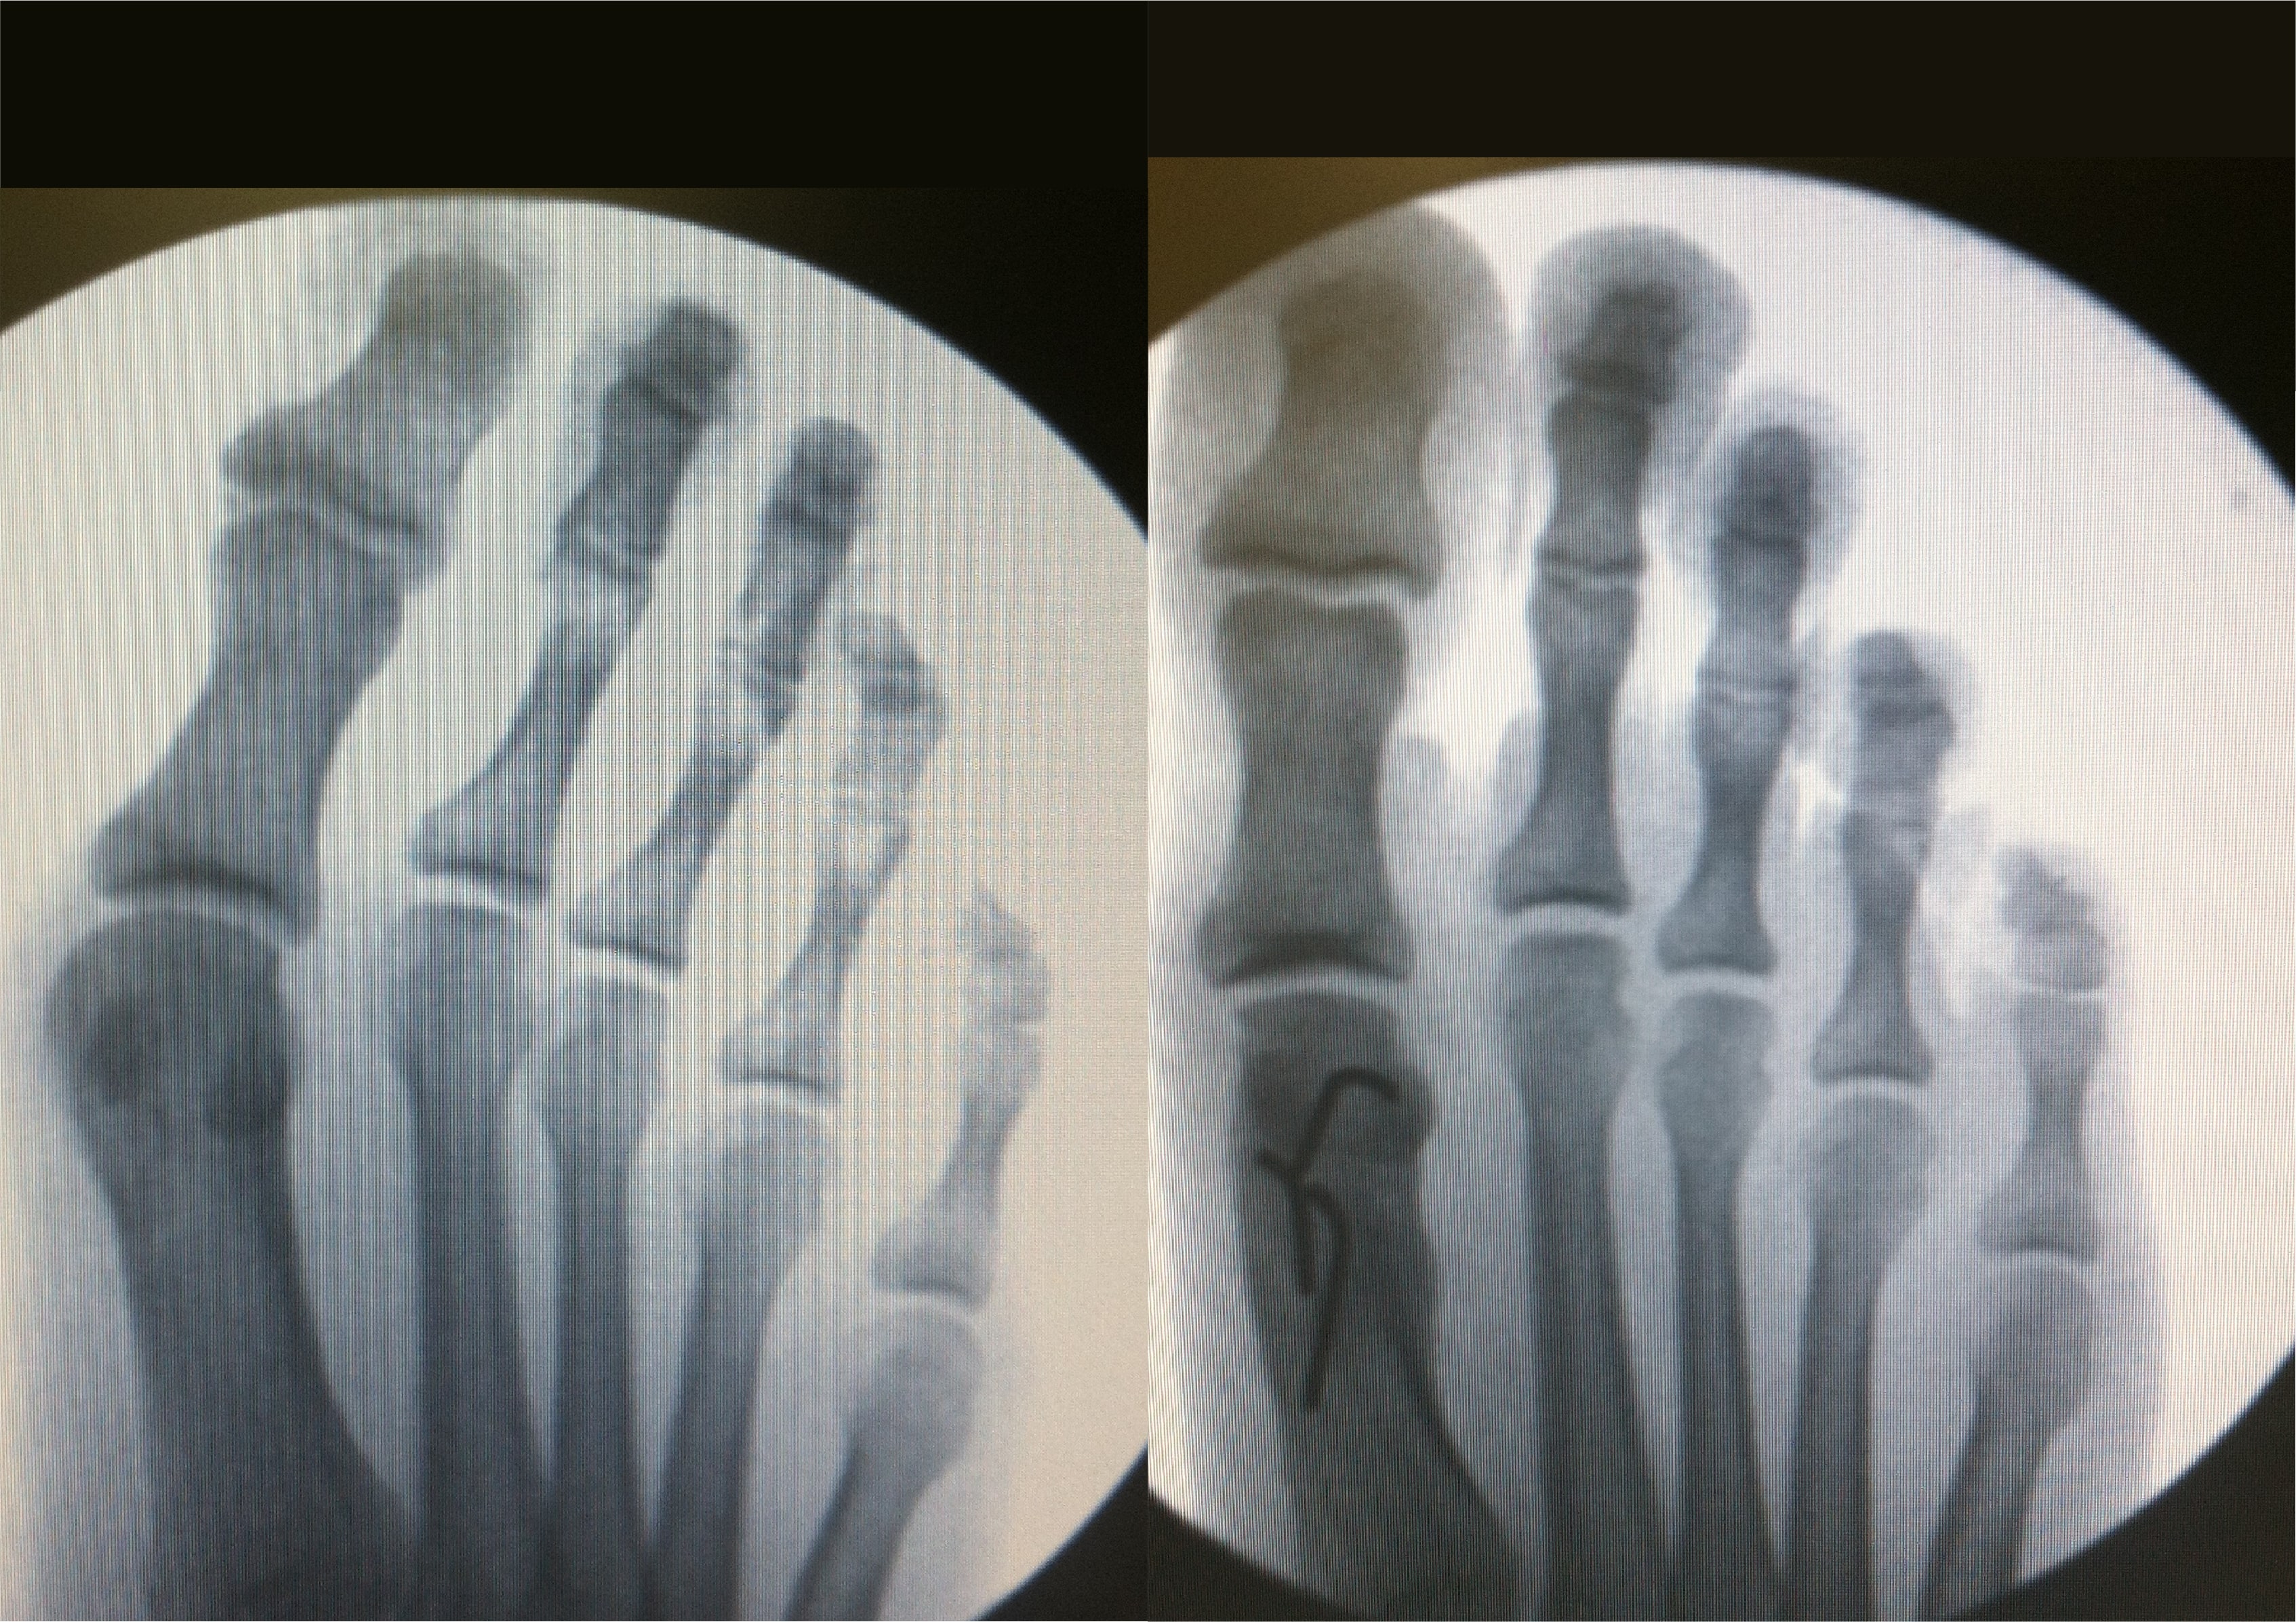

Bunions

Before

After